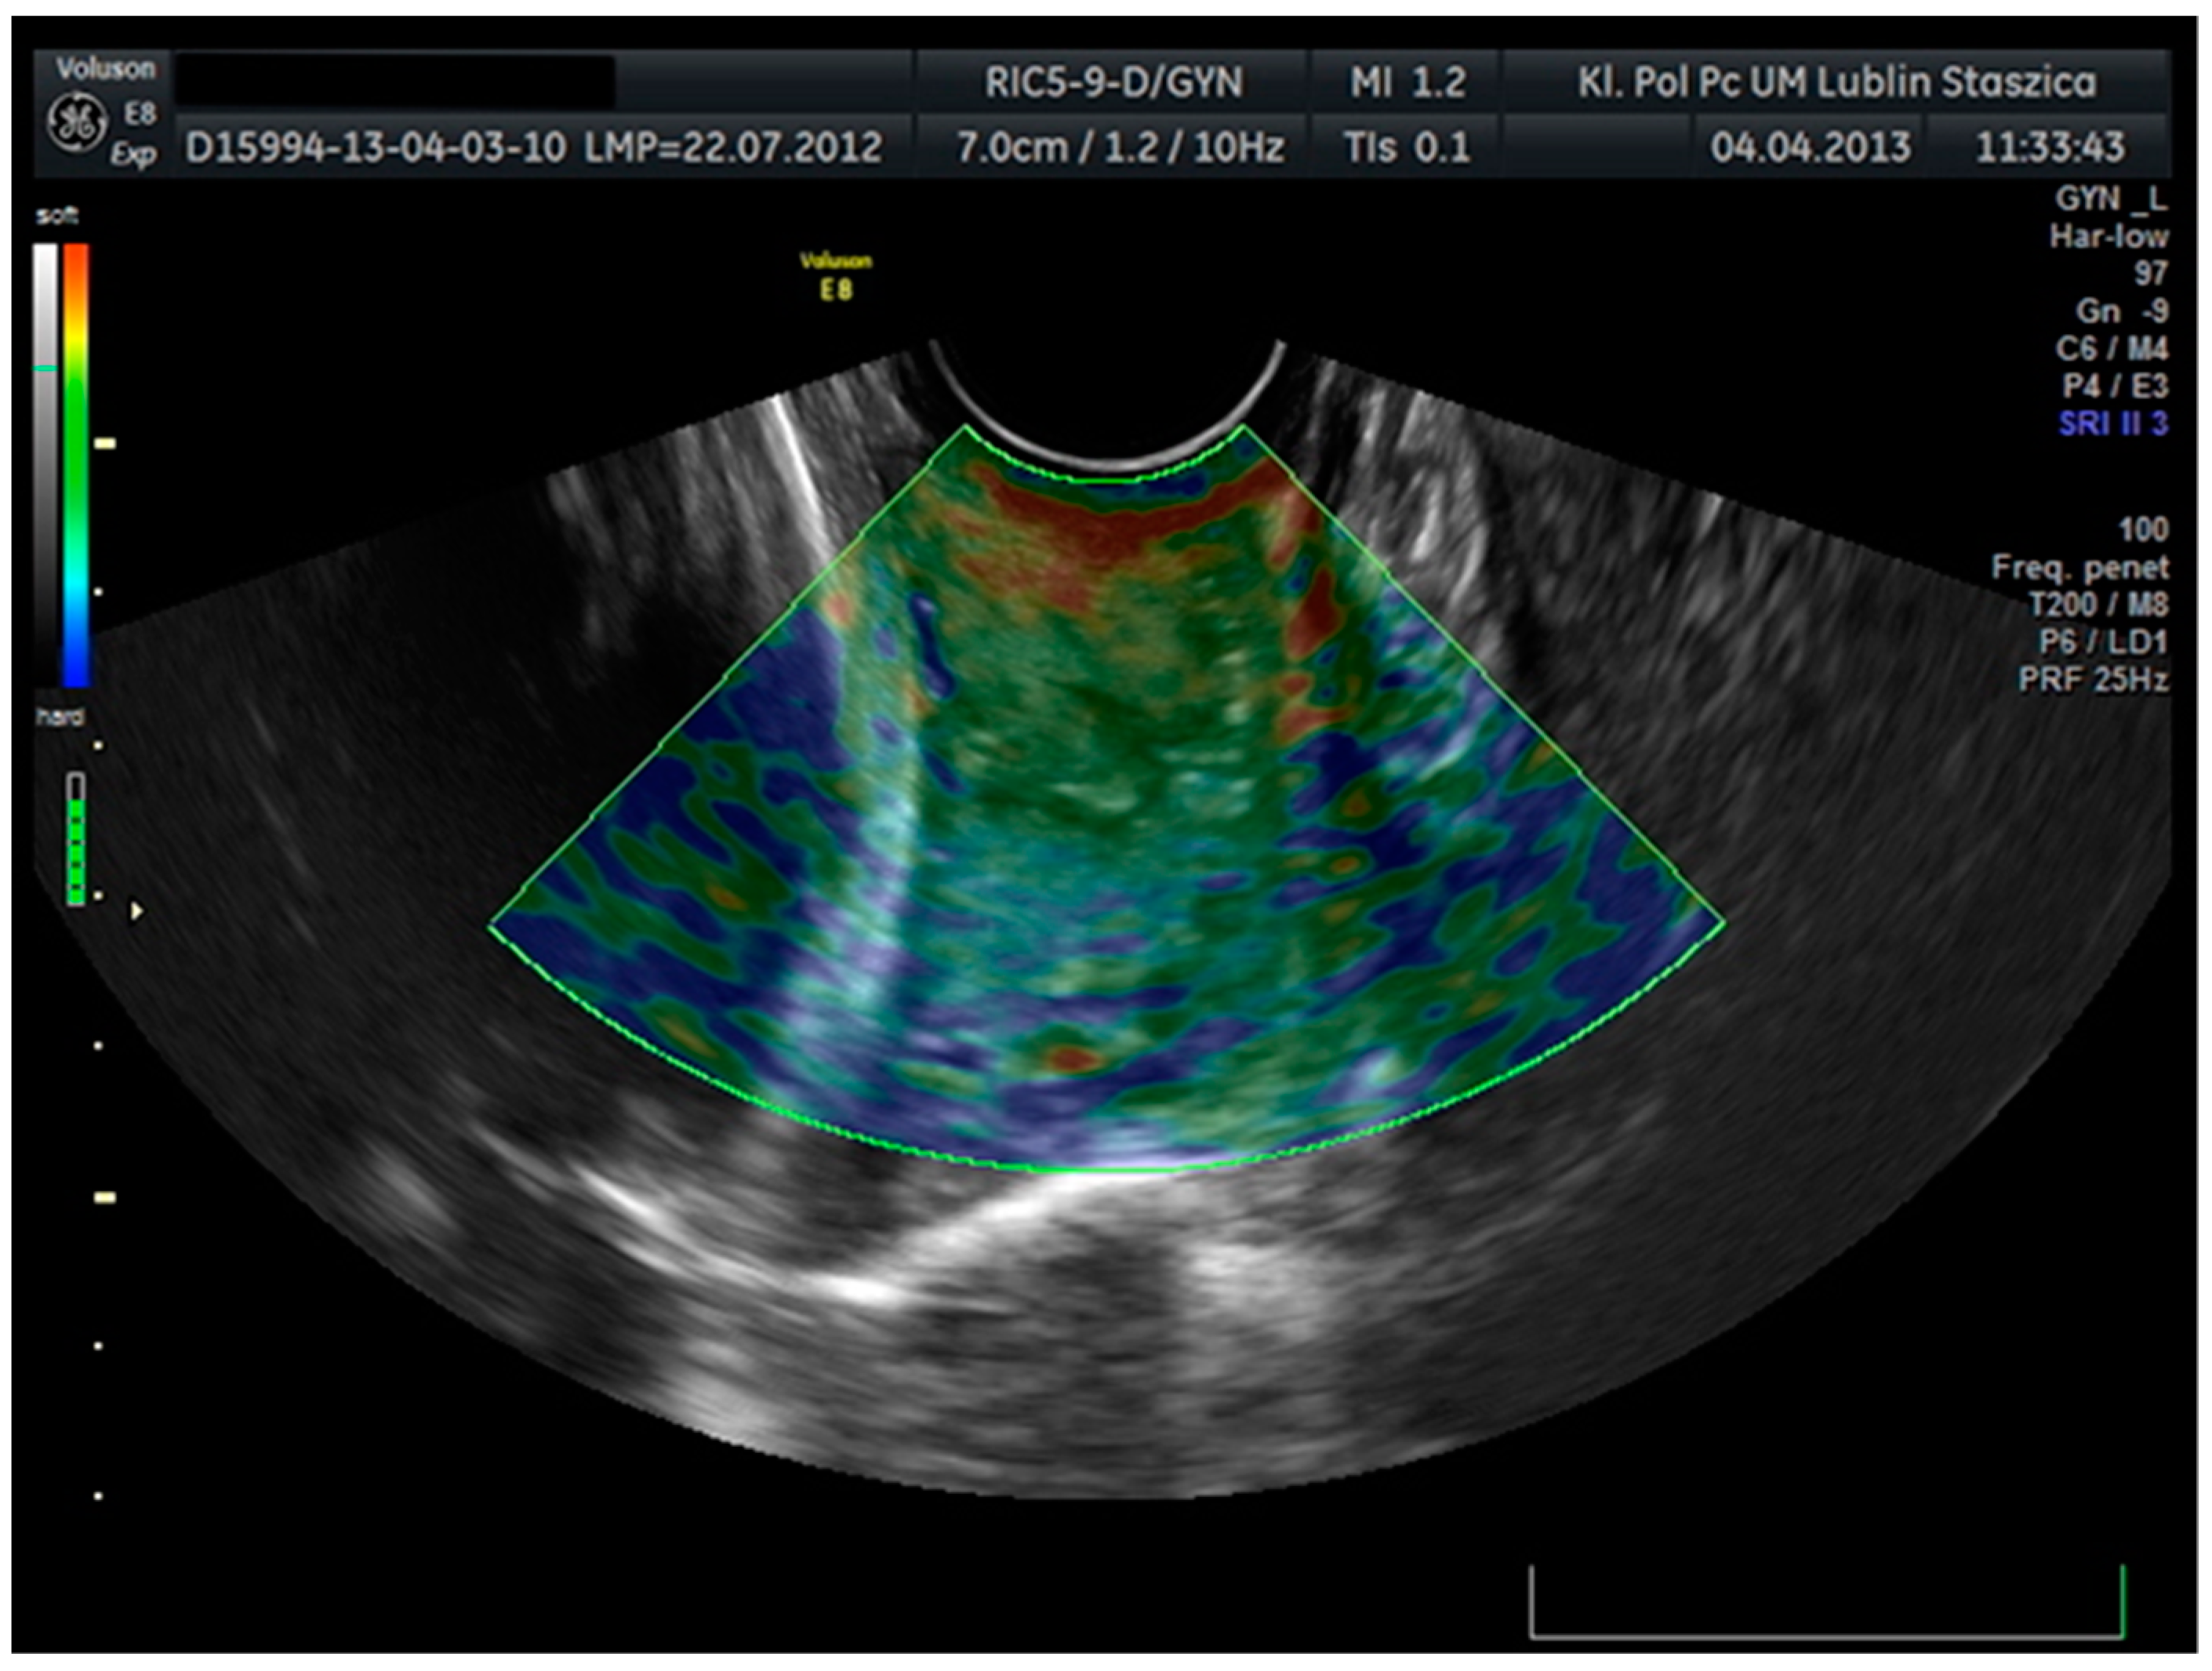

The transducer receives two sets of radiofrequency signals: before and after squeezing the cervix, and the amount of shift in the tissue is estimated from the waveform difference. Tissue rate versus distance from the transducer is calculated for all image points. The rate of change values are known as strain values and are displayed in a variety of colors ranging from red to yellow, green to blue for soft and hard tissues. Tissues marked in red are considered to be the most flexible tissues, while tissues with the least elasticity are marked in blue (Figure 2).

Figure 2. Cervical elastographic assessment. Tissue elasticity distribution calculations in real-time and presented using a color scale—red (soft), blue (hard), and green (medium-hard).